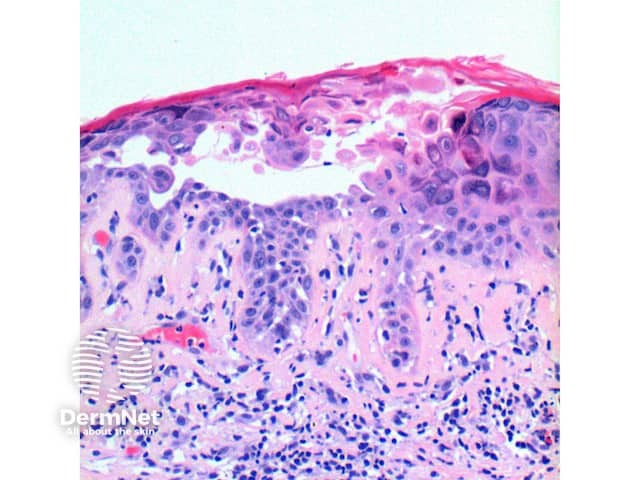

The scanning power view of the histology of Darier disease is of an epidermal and superficial dermal inflammatory process (Figure 1). Intraepidermal separation may be visible at this power, which on closer inspection is seen as suprabasal acantholysis (Figures 2 and 3). Acantholysis can be seen at all levels within the epidermis. Dyskeratosis of the keratinocytes is seen, with two notable changes described. Corps ronds refer to cells with small pyknotic nuclei, a perinuclear clear halo and eosinophilic cytoplasm (Figures 4 and 5).

In the superficial dermis is a mild predominantly perivascular lymphocytic infiltrate (Figure 2). Eosinophils are rarely seen.

Figure 2